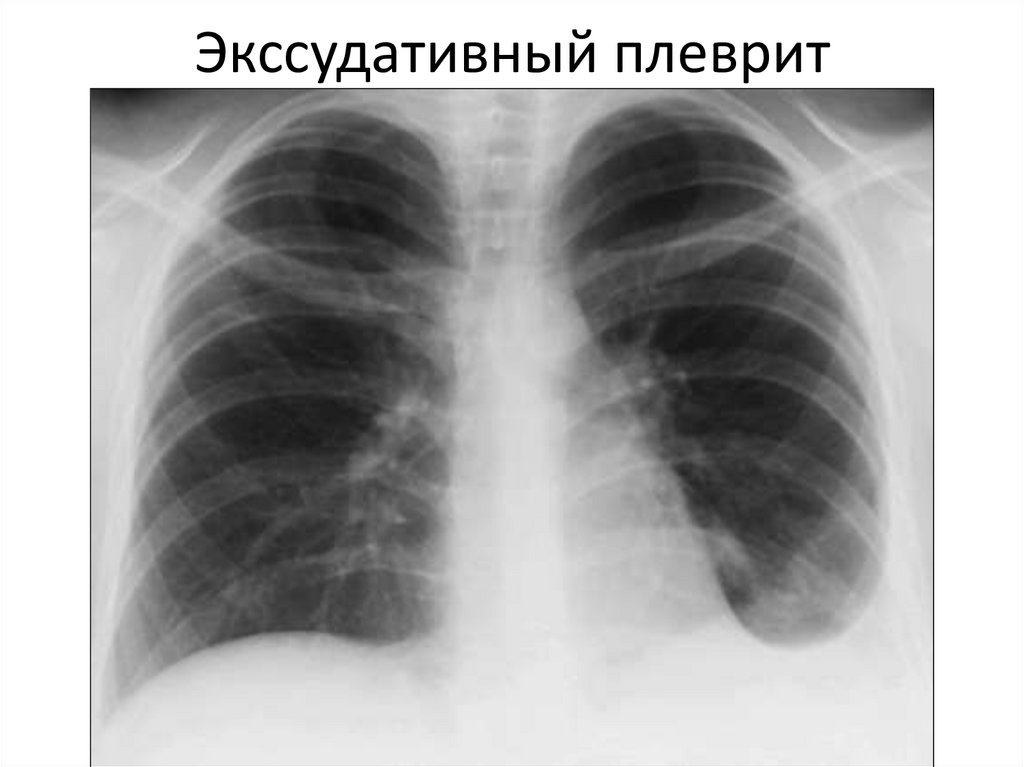

Экссудативный плеврит

Пневмоторакс Гидроторакс

затенение

гомогенное

Смещение

средостения в

противоположную

сторону